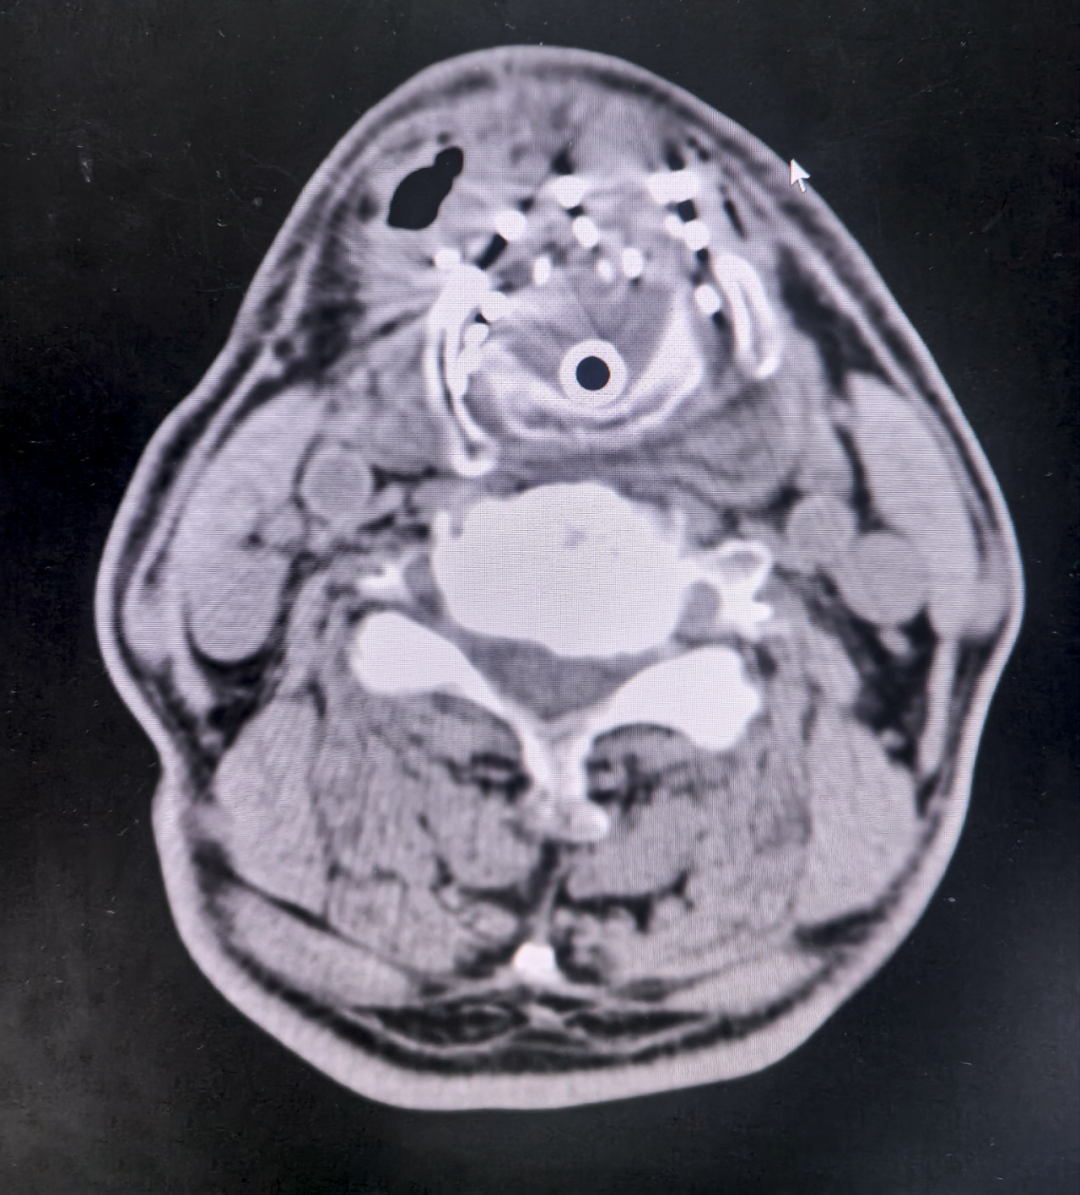

手术全程在CT影像实时导航下进行,11根18G穿刺针以0.5mm精度植入55粒碘125粒子。这种被称为"肿瘤内放疗"的技术,通过持续释放低剂量γ射线,能在保护正常组织的同时对癌细胞进行"定点清除"。

1、三维立体定位:通过TPS(治疗计划系统)预先计算粒子分布,确保辐射剂量覆盖肿瘤又不损伤声带、气管。

2、动态调整机制:术中两次CT扫描比对,及时修正穿刺角度偏差。